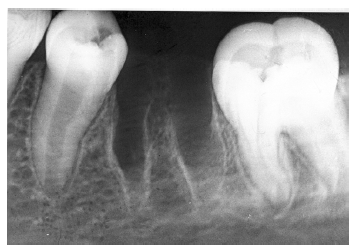

Figure 3 - Dentin Caries

Figure 3

Dentin caries extends into the tooth dentin and can be recognized by noting the focal loss of dentinal radiopacity. Most commonly, this darkened dentin is located beneath carious enamel and, typically, the lateral dimension of the dentinal involvement exceeds that of the associated enamel caries (Figure 3). Dentin caries may be discerned interproximally, on the occlusal surface, buccally/lingually, or on root surfaces.